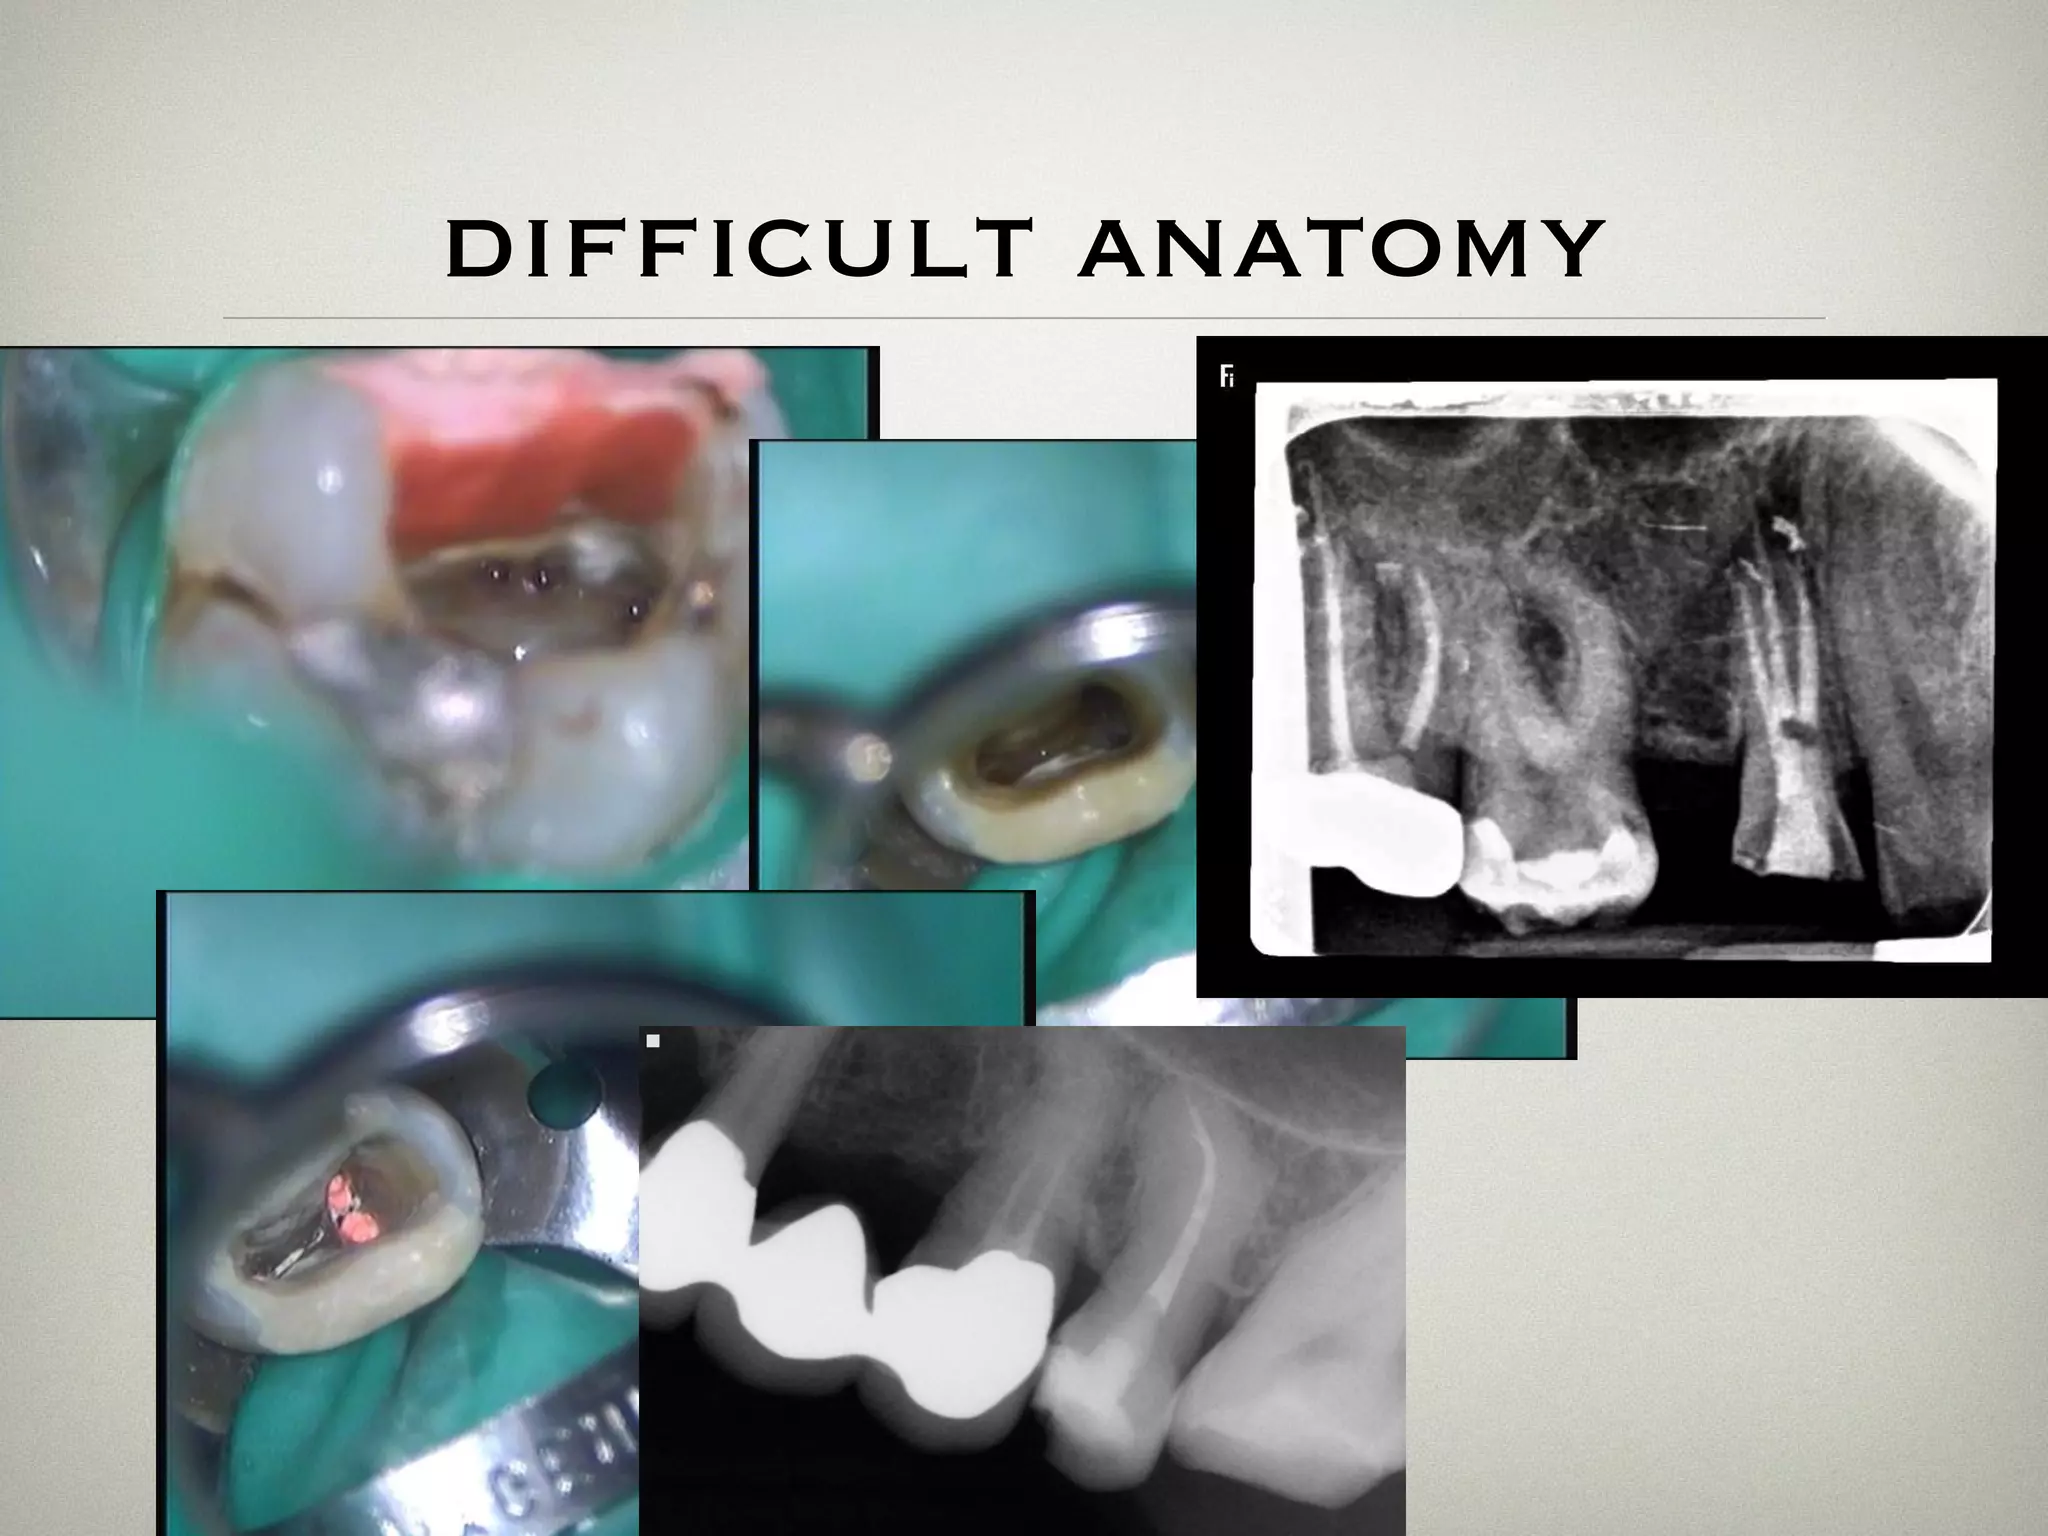

difficult anatomy

labial access to lower

incisors